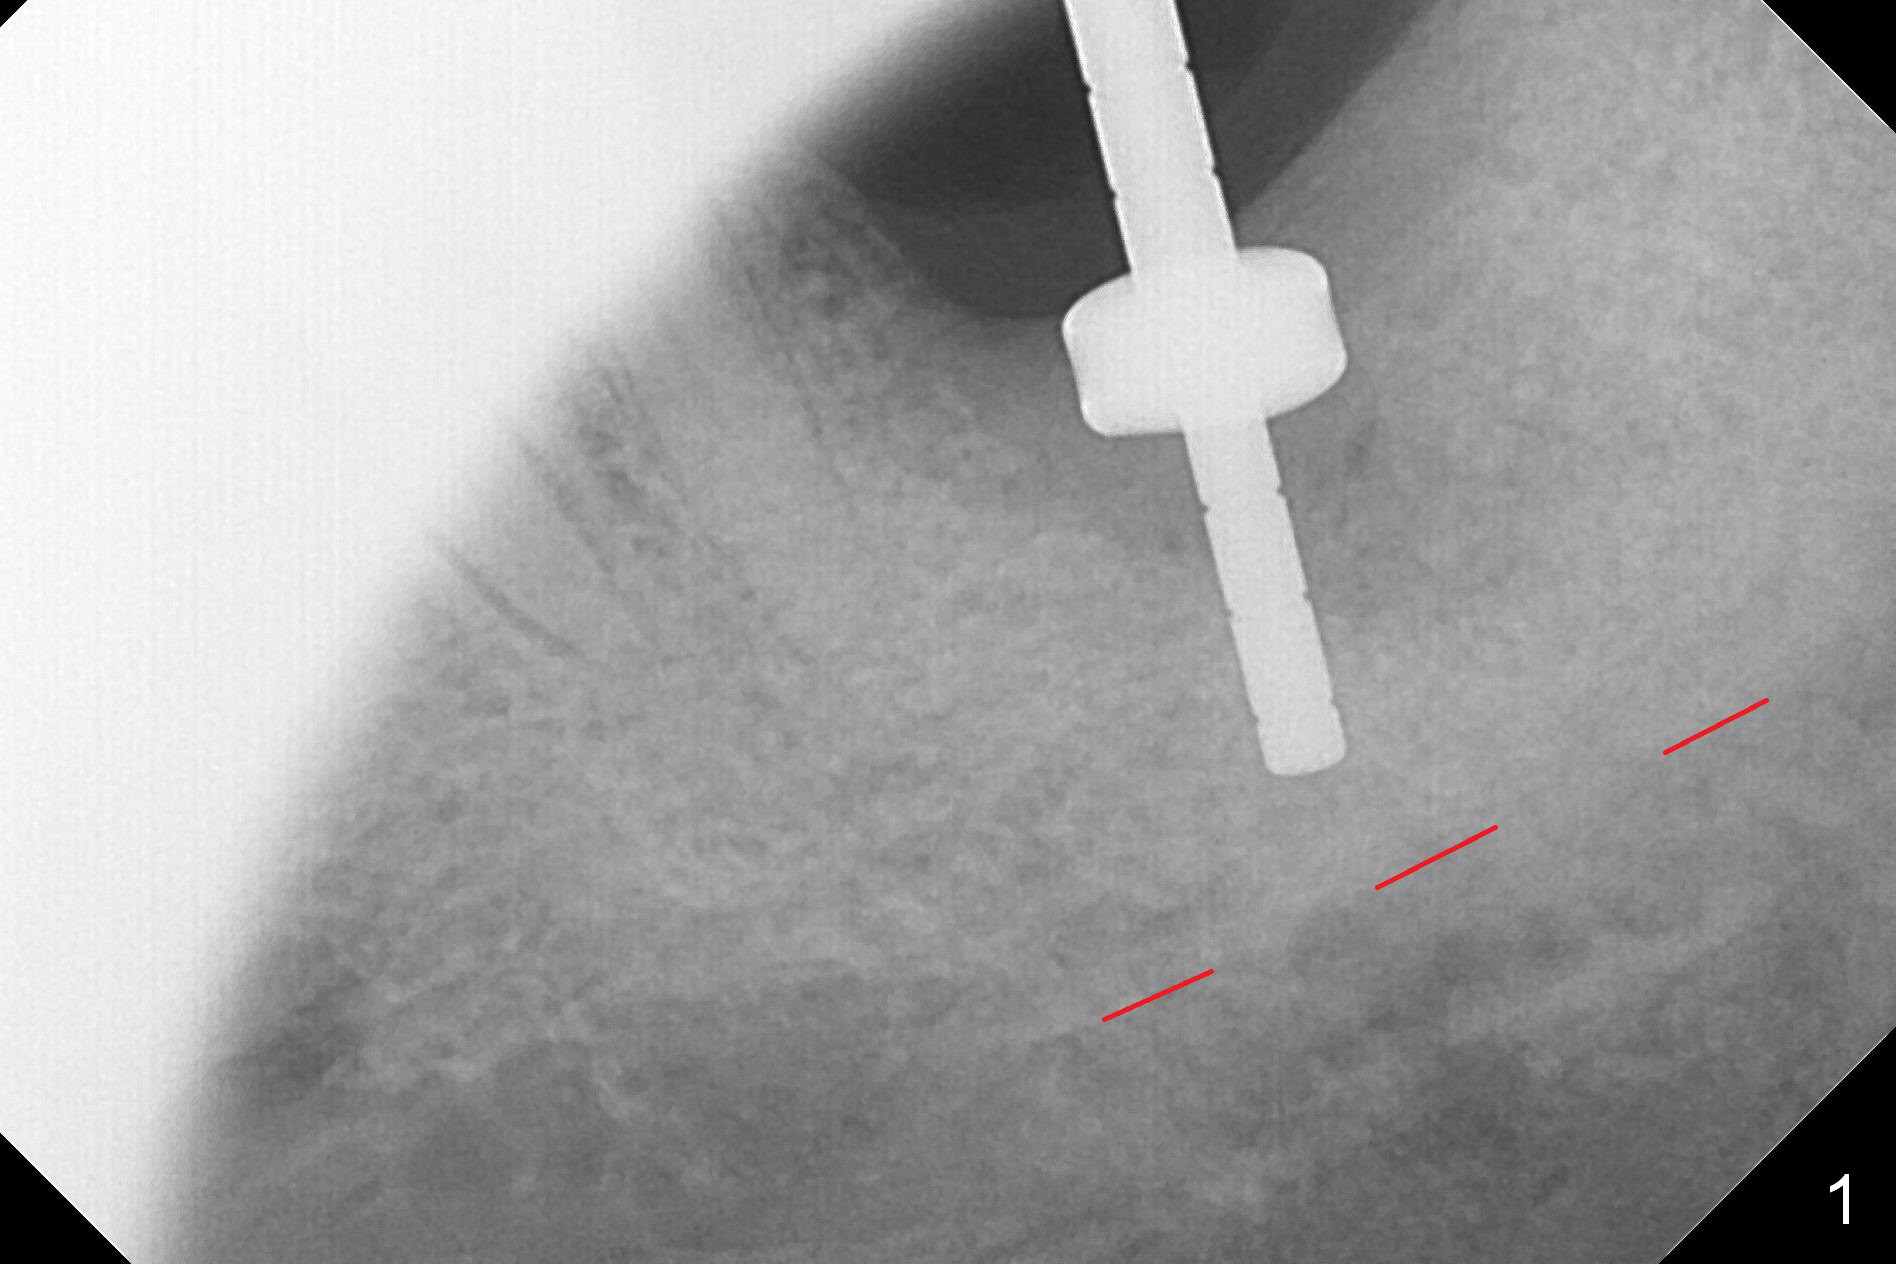

When the tooth #18 is extracted, the buccal and lingual plate are absent. Initial osteotomy is established in the middle of the socket (Fig.1). After 4.3 mm Magic Drill (15 mm from the buccal gingival margin, new bone ~ 4 mm), a 5x9 mm IBS dummy implant is placed with correct trajectory (Fig.2). Since the bone density is seemingly high, the same size of a definitive implant is placed with primary stability. The trajectory is found not ideal after bone graft and insertion of an abutment (data not shown). The stability is lost when the trajectory is changed. No primary stability is achieved with a larger (5.5x9 mm) implant. Tatum tapered taps (6x17, 7x17 and 8x17 mm) are used. The latter obtains stability with contact with the mesial and distal crests (Fig.3 *). A 8x14 mm tissue-level implant is placed with insertion torque ~ 55 Ncm (Fig.4). A 6x3 mm abutment (Fig.4 A) is placed to retain an immediate provisional (Fig.5 P). The drawback of the extra large implant is lack of bone buccolingually. Oral hygiene is emphasized so that the buccal and lingual bone have chance to regenerate. Fortunately there appears to be no paresthesia postop.